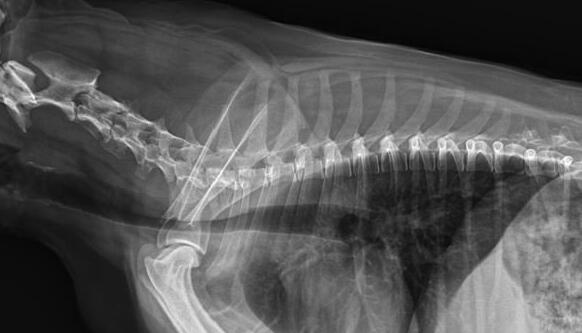

利用寵物dr拍攝圖像效果圖

1、DR的DQE檢測效率可達74%,而傳統普通膠片組合X線照片DQE為30%。

2、寵物DR成像速度快,采集時間10ms以下,成像時間僅為3秒,對于受傷的寵物來說,檢查越快速,越能早點幫助其治療,降低痛疼。對于寵物主人而言,也是一種心理安慰。

3、數字圖像可進行后處理。圖像后處理是數字圖像的很大特點。只后要保留原始數據,就可以根據診斷需要,并通過軟件功能,有針對性的對圖像進行處理,以提高診斷率。

4、獸用dr所具備的輻射劑量較低,相比傳統的ct而言,對于寵物和醫生而言,都是一種保護。

5、有效解決了圖像的存檔管理與傳輸,采用光盤刻錄形式保存圖像資料,隨時能為受檢者提供照片打印服務,這樣大大提高了工作效率。對于接診量比較大的寵物醫院來說,這個具備大的優勢。